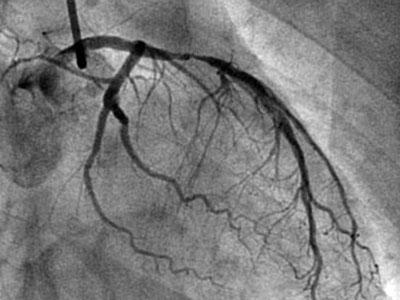

很多心脏病患者对于植入冠心病支架还是持有抵触的态度,即使造影提示血管狭窄了90%,医生建议支架手术。不少心脏病患者问过我,“如果冠状动脉狭窄90%,就是只吃药,不放支架会怎样?”

很多心脏病患者口中都流传着某某患者坚持只吃药,不放支架,复查造影时居然血管狭窄减轻的传说。其实,我也见过类似病例,但是并不是血管狭窄90%这种严重情况。有的患者是弥漫性的血管病变,血管狭窄60%-75%左右,斑块不稳定,血栓负荷较重,通过口服抗血小板药物,复查造影时会因为斑块的稳定和血栓负荷的减轻出现影像学上的狭窄减轻。

但这仅仅是在造影这种二维图像上的表现,固有的狭窄病变往往并不会减轻。